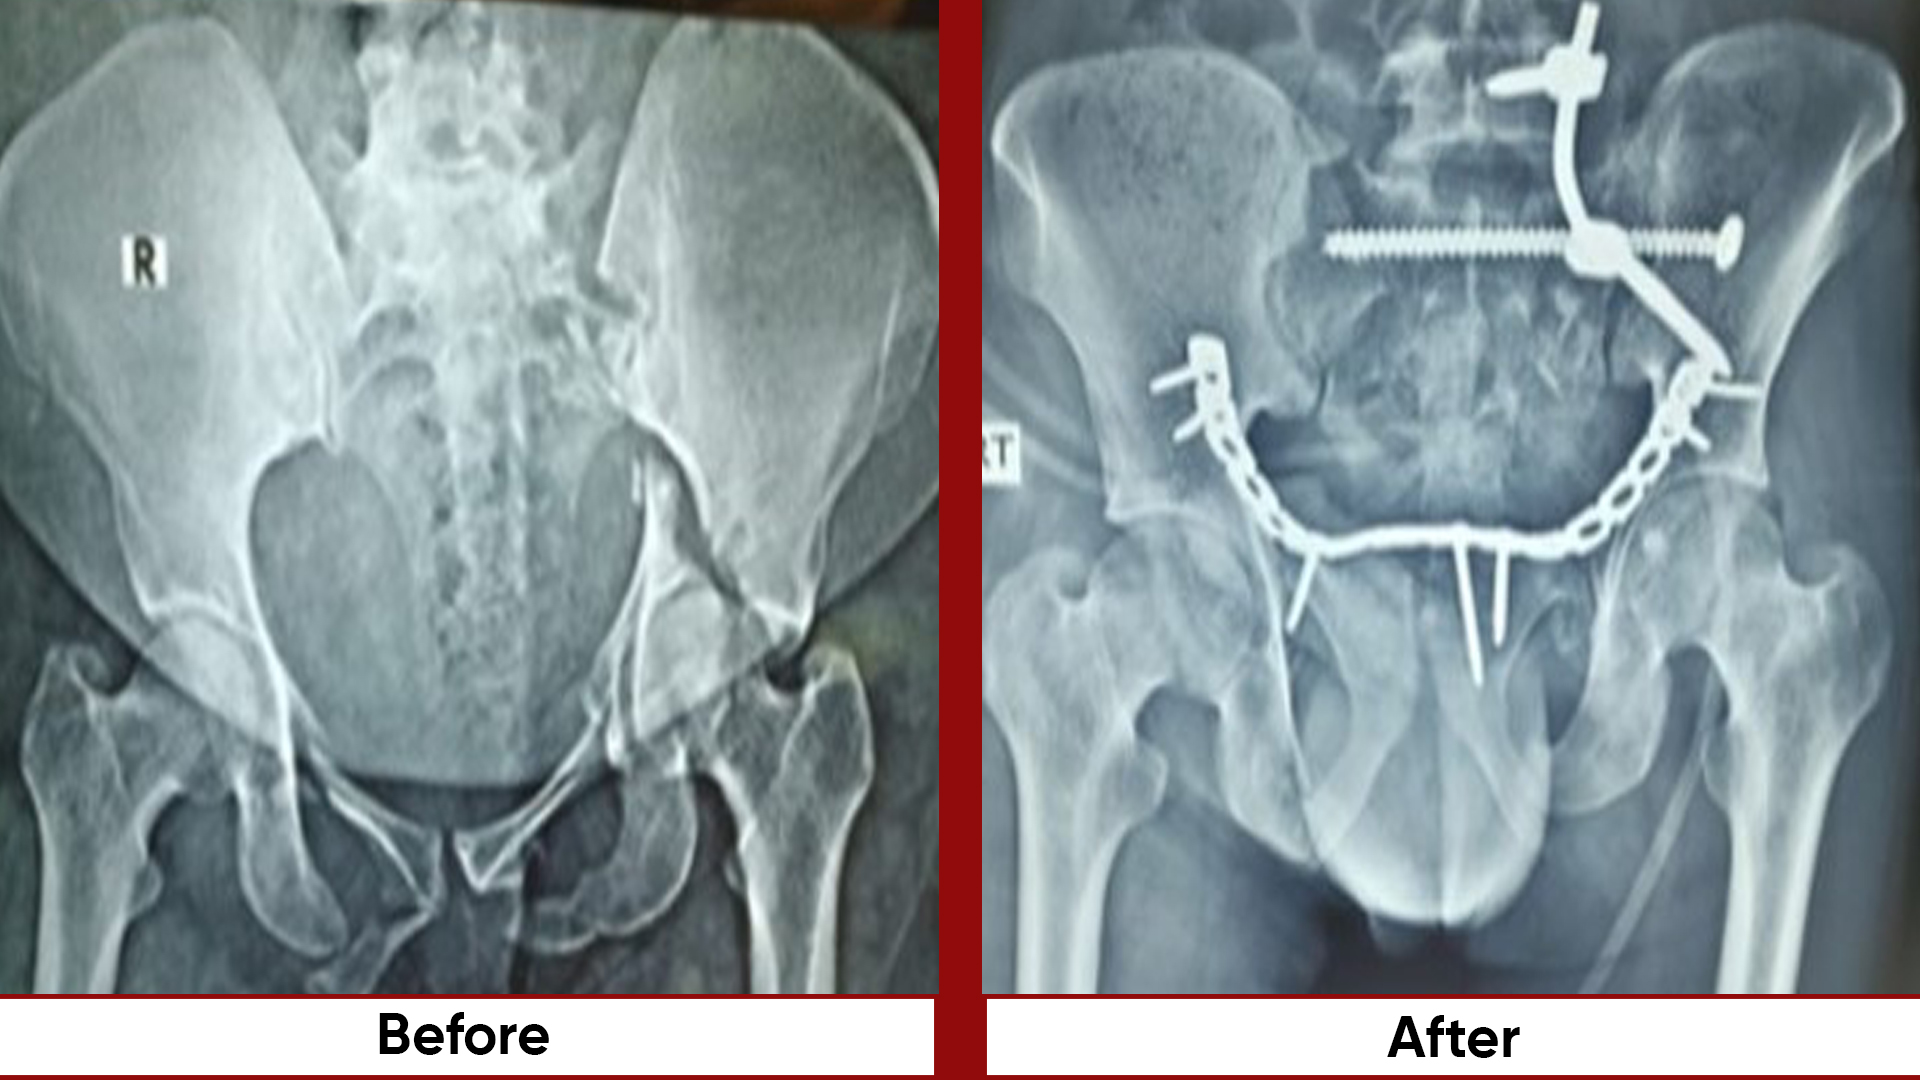

• Fracture Management (simple and complex trauma)

• Pelvic & Acetabular Fracture Fixation